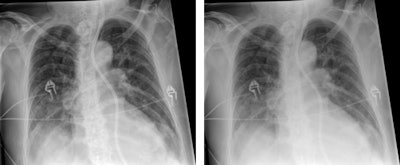

Tomosynthesis image of an ankle taken with Shimadzu's RADspeed Pro digital radiography system.The emphasis of Philips' researchers has been on developing technologies for improving diagnostic quality while eliminating inefficiencies when using mobile digital radiography systems at the patient's bedside. The new SkyFlow scatter correction algorithm reduces the effect of scattered radiation for nongrid bedside chest exams, allowing the operator to obtain DR images with grid-like contrast, but avoiding the time and effort involved in attaching and detaching a grid.

Pelvic radiographs taken with and without SkyFlow scatter suppression algorithm. Image courtesy of Philips.

Chest radiographs taken with SkyFlow scatter suppression algorithm and standard acquisition. Image courtesy of PhilipsOn the GE Healthcare stand, its representatives are keen to discuss new evidence showing the clinical value of its long established digital tomosynthesis technology, VolumeRAD. A recently completed international multicenter clinical trial has demonstrated that the product offers improved detection and management of patients with lung nodules compared with conventional radiography – with a 7.5 times increase in sensitivity for nodules between 4 mm and 6 mm diameter compared with standard x-ray. The device is reportedly 3.6 times more sensitive than conventional two-view computed radiography, without decreased specificity of detection of small lung nodules in the range of 3 mm to 20 mm in diameter.